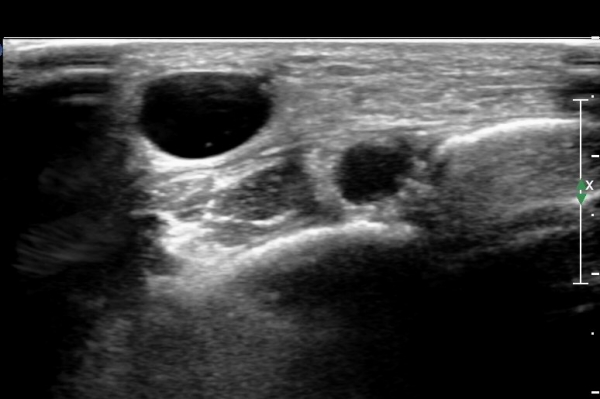

¾ÕÂÊ ¸»´Ü °æ°ñºñ°ñ°üÀý ¾à 5cm ±ÙÀ§ºÎ Ⱦ´Ü몀°Ë»ç ½Ã õºñ°ñ½Å°æ Àü¸é¿¡ Àú¿¡ÄÚ ³¶Á¾¿¡ ÀÇÇÑ ½Å°æ ¾Ð¹ÚÀÌ °üÂûµÈ´Ù(ÀÌ °üÂûµÈ´Ù(»çÁø 6, 7).

¸»´ÜÀ¸·Î °¥ ¼ö ·Ï ³¶Á¾ÀÌ Ä¿Áø°í õºñ°ñ½Å°æ ¾Ð¹ÚÀº ½ÉÇØÁø´Ù(»çÁø 8).

³¶Á¾À» Á¾´Ü¸éÀ¸·Î °üÂûÇÏ´Ï ³¶Á¾ÀÌ ¸»´Ü °æ°ñºñ°ñ°üÀý¿¡¼ À¯·¡µÊÀÌ È®ÀεȴÙ(»çÁø 9).